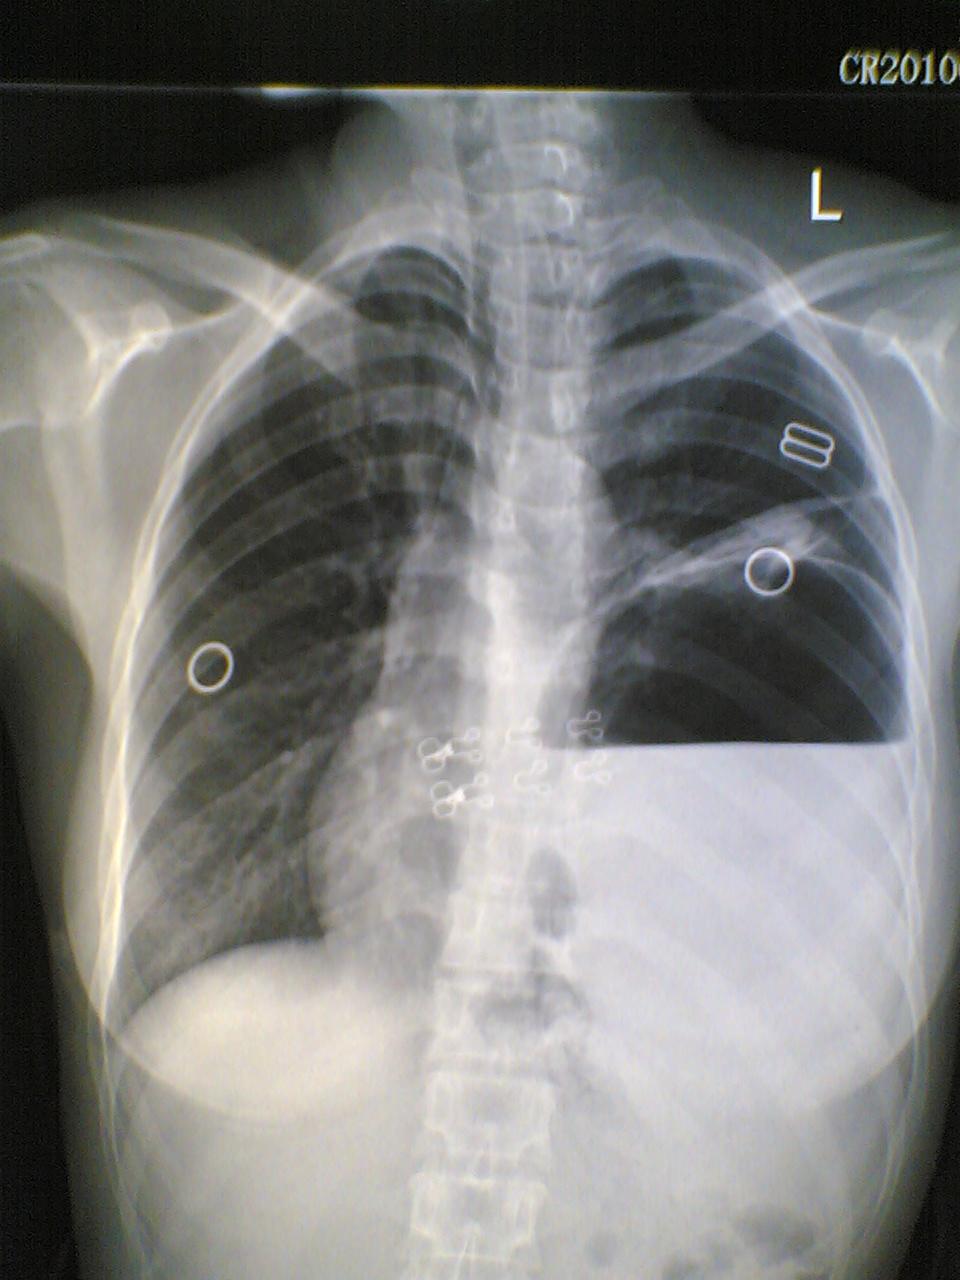

标题: X7060:女,40,呕吐一日,自觉上腹部不适,剑突下痛。 [打印本页]

标题: X7060:女,40,呕吐一日,自觉上腹部不适,剑突下痛。

膈疝?膈膨升?胃泡上是膈面还是肺组织?请各位老师多多指教(图像质量欠清,包涵)

1)考虑左侧膈疝。2)左下肺盘状肺不张。

左侧膈疝,伴胃扩张,左下肺膨涨不全(压缩所至)。

左侧膈疝,左下肺盘状不张。

1)考虑左侧膈疝。2)左下肺盘状肺不张。支持!应该做钡餐或透视进一步检查。